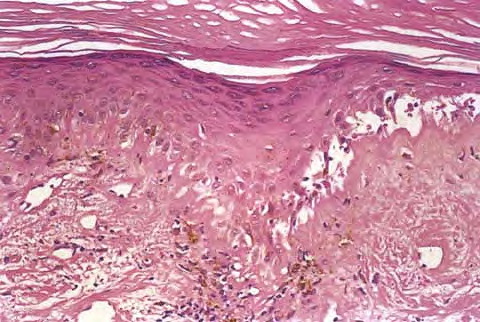

Discoid LE= الذئبة الحمامية القرصية